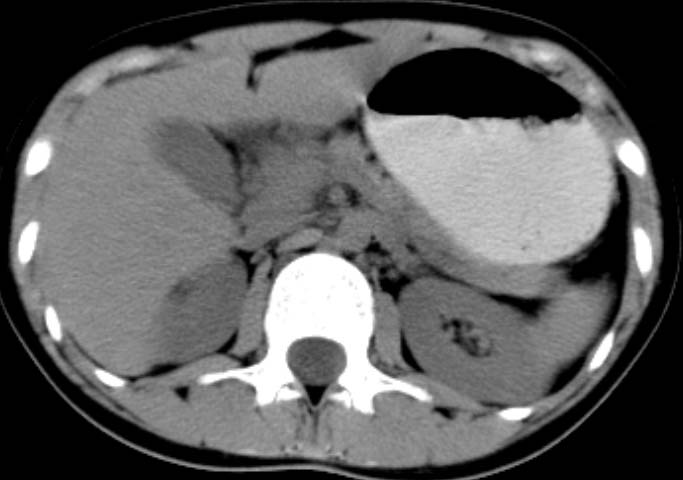

女,14岁。腹痛3天。腹部触诊未触及包块。碘剂阳性未增强。求助战友。。。。。。。。。。。

胰头部明显肿大,胰周间隙浸润,考虑胰腺炎可能性大

胰头部增大,周围模糊,有渗出,胰腺炎可能性大,建议结合化验检查;左侧输尿管上段略扩张.

胰头部明显肿大,胰头周脂肪密度加大。十二指肠环扩大受压。胰管未见确切扩张。考虑胰腺炎可能性大。建议增强扫描。

胰头部增大,周围结构模糊,并明显见渗出。支持:急性胰腺炎!

1)急性胰腺炎。2)肝右叶后上段肝内胆管结石。3)左侧输尿管上段扩张,原因待查。

胰头明显肿大呈肿物样,周围脂肪密度增高,结合病人年龄及临床表现,首先考虑炎性改变,建议结合实验室检查明确。必要是复查或mr检查

病灶应在胰头下区,不一定是胰头,结合周边低密度水肿,是否可能为十二指肠(xi)室炎症或其它炎症。

胰周无明显渗出,吉氏筋膜未见增厚。血尿试验室检查不支持。排除胰腺炎。